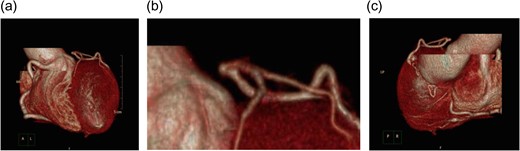

A 62-year-old woman presented with exertional chest pain. She visited our hospital because her symptoms were gradually intensifying for several years. Her only risk factor for heart disease was hypertension; she had no history of smoking, and she did not have dyslipidemia. Electrocardiography did not show any ischemic changes. On echocardiography, left ventricular function was preserved and neither hypokinesia nor valvular heart disease was observed. Further evaluation of coronary artery disease was considered necessary; therefore, she underwent a detailed examination using coronary computed tomography (CT) (Fig. 1), which revealed an LMT occlusion. Coronary angiography also revealed that the LMT was occluded at the origin. The entire left coronary artery was visualized through collateral circulation in right coronary angiography (Fig. 2). Based on blood test findings and aortic CT results, arteritis and autoimmune disease were ruled out.

Coronary CT is also useful for diagnosis of occlusion of coronary artery [4]. Coronary CT enabled us to make a diagnosis of LMT-CTO and to make plans of surgery. Furthermore, aortic CT can be performed simultaneously with coronary CT, thus enabling simultaneous screening for aortitis and other systemic vascular diseases.